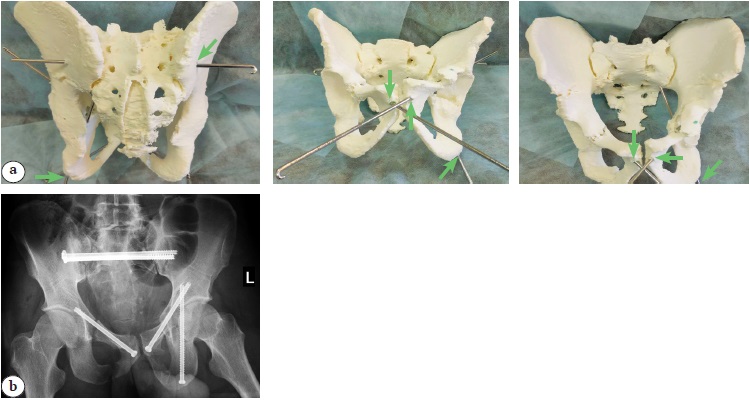

The next step involved analyzing the resulting physical 3D model, discussing the clinical case to determine the surgical strategy, selecting the appropriate types and sizes of implants, assessing the associated risks of minimally invasive surgical treatment, and evaluating the accessibility and positioning of optimal safe bone corridors under visual control and using a C-arm (Figure 2).

Figure 2. Evaluation of accessibility and positioning of optimal safe bone corridors: a — visual control (green arrows indicate access points to safe bone spaces); b — X-ray control after surgery using the obtained 3D model

The obtained results were documented photographically (Figure 3).

Figure 3. Photograph of 3D model of the pelvic bones with wires (a) introduced in the S1 body and X-ray images of their position (b)